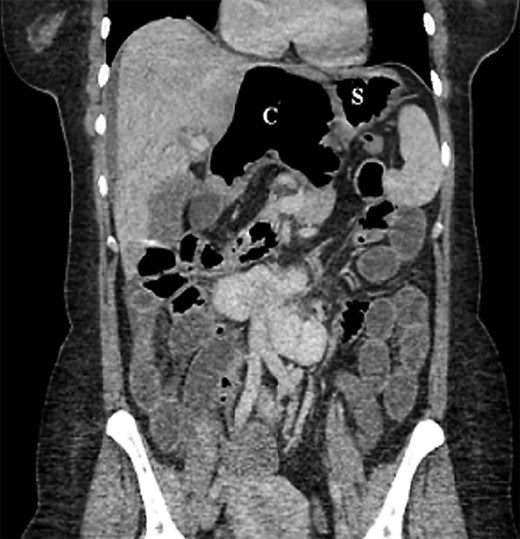

Laboratory investigations, including a complete blood count, urea and analysis, and coagulation profile, were all within normal limits. An abdominal X-ray showed a dilated large bowel with few air fluid levels, no gas in the rectum and no air under the diaphragm (Fig. 1). An abdominal CT scan with oral and intravenous contrast showed that the cecum was flipped superiorly and positioned anteriorly to the transverse colon, and it herniated into the foramen of Winslow (opening between the inferior vena cava and portal vein). The cecum occupied the lesser sac, and it was distended with gas and caused a mass effect on the stomach and hepatic root, with associated intrahepatic bile duct dilatation. This was associated with proximal small bowel dilatation and collapsed large bowel loops distally (Fig. 2). These findings were consistent with an obstructive internal hernia into the lesser sac through the foramen of Winslow.

Coronal section of abdominal computed tomography scan showing the cecum (C) flipped superiorly and positioned anterior to the transverse colon and herniated into foramen of Winslow. The cecum occupies the lesser sac, and it is distended with gas, causing a mass effect on the stomach (S) and hepatic root with associated intrahepatic bile duct dilatation. This is associated with proximal small bowel dilatation and collapsed large bowel loops distally.